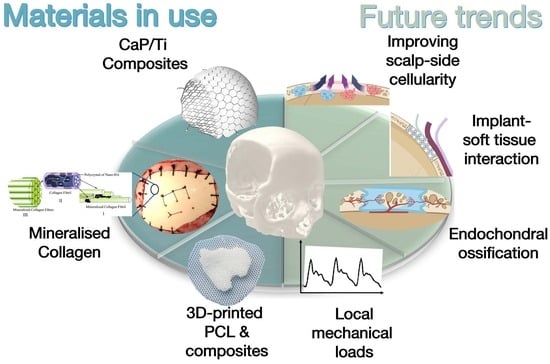

2. Regeneration Capacity of Cranium

2.1. Biological Basis of Cranium Regeneration

2.2. Clinical Observation of Cranium Regeneration